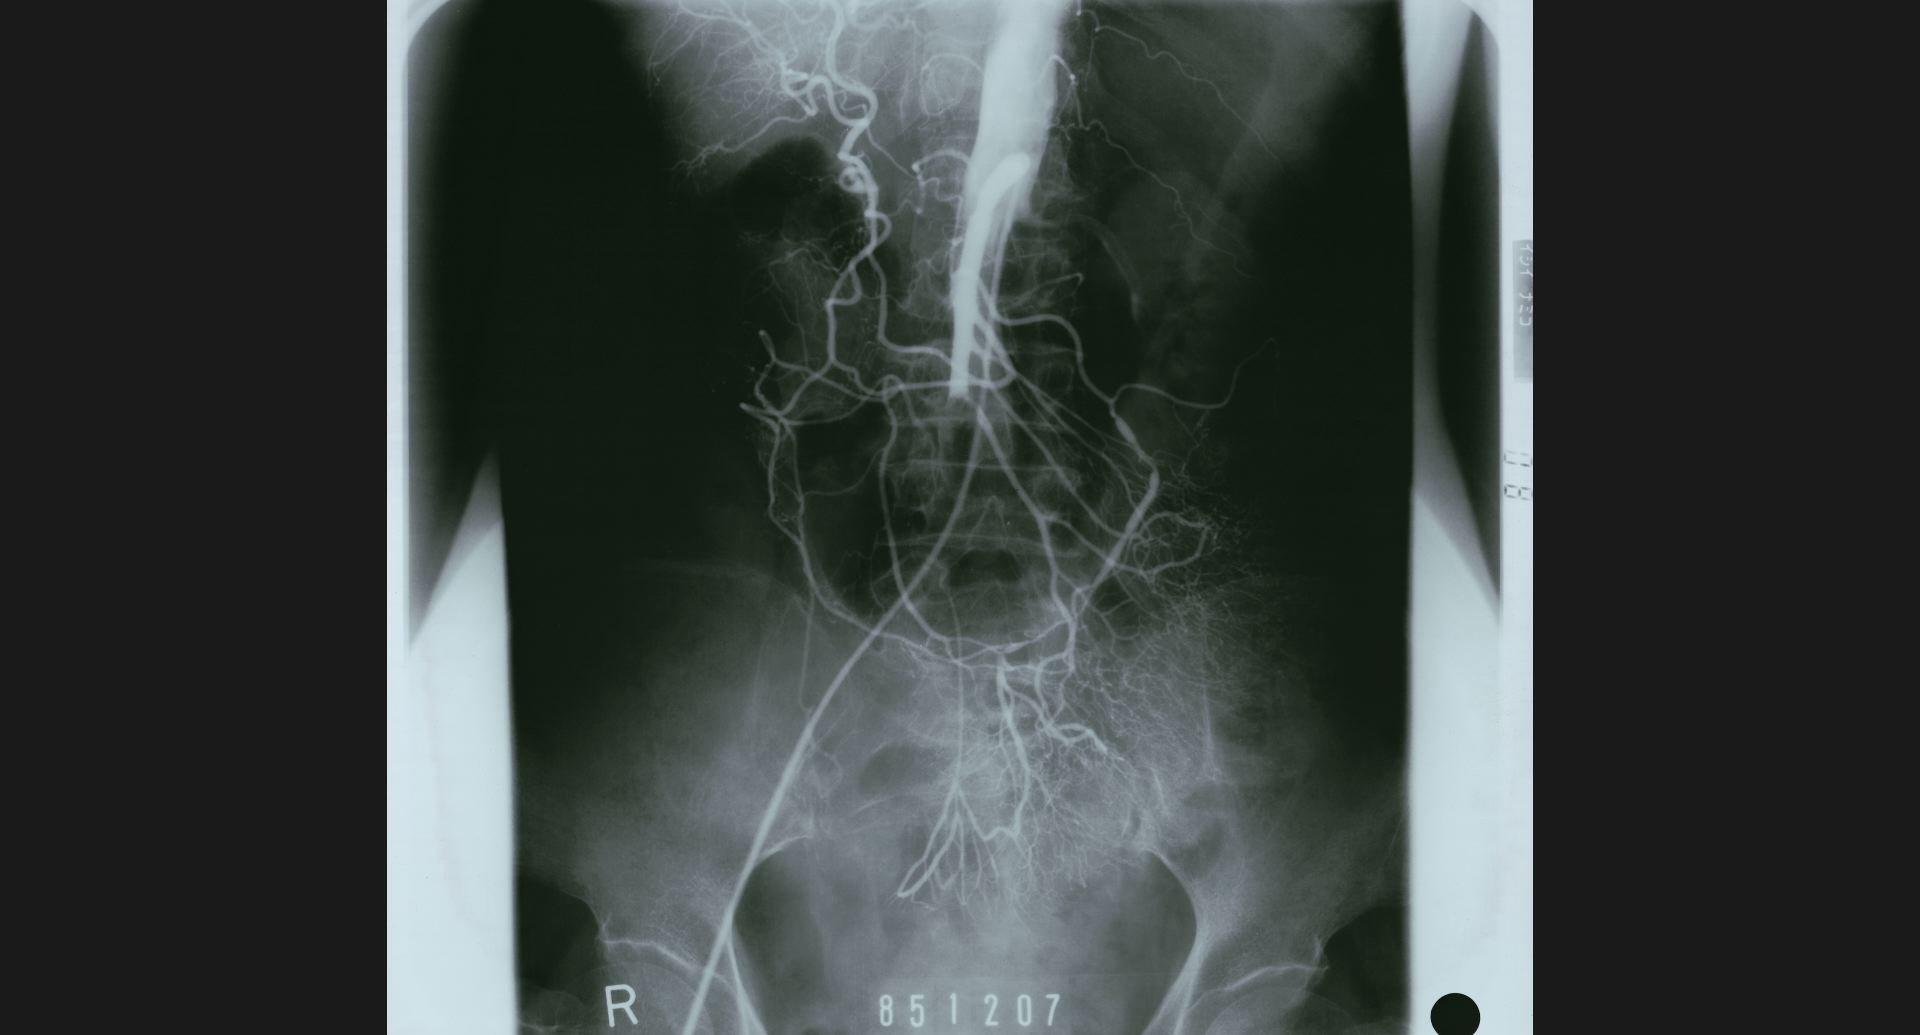

fig.10(99KB)

:SMA thrombosis (angiography)閉塞部位。腸管壁の細かい動脈。